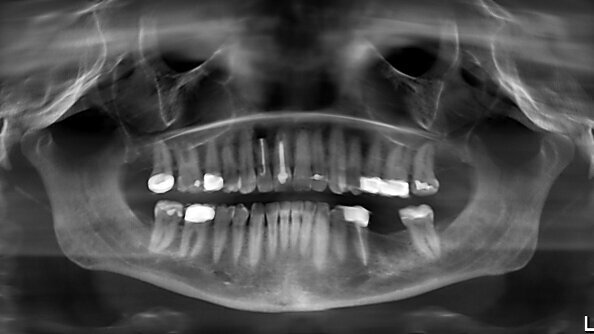

Le patient s’est présenté à l’équipe de soins en formulant le souhait d’une restauration prothétique implanto-portée au niveau de la position dentaire 36. Les antécédents médicaux généraux du patient ne présentaient aucune anomalie. L’état bucco-dentaire n’indiquait aucun besoin réel de traitement. La denture du maxillaire était complète mais une radiographie avait permis de diagnostiquer un kyste radiculaire touchant la dent 12, dont le traitement chirurgical est prévu dans un avenir proche. Une image similaire se dégageait de la mandibule. Après la fermeture de l’espace en position 36 et la restauration de la dent 12, le traitement sera donc terminé. La radiographie initiale (un OPG) avait indiqué une dimension verticale suffisante de l’os (Fig. 1), mais un manque de volume osseux vestibulaire d’un point de vue clinique, confirmé ensuite par imagerie tridimensionnelle (tomographie volumique numérique).

Fig. 1_Radiographie (OPG) de la situation initiale. L’espace en position dentaire 36 doit être fermé par une prothèse implanto-portée.